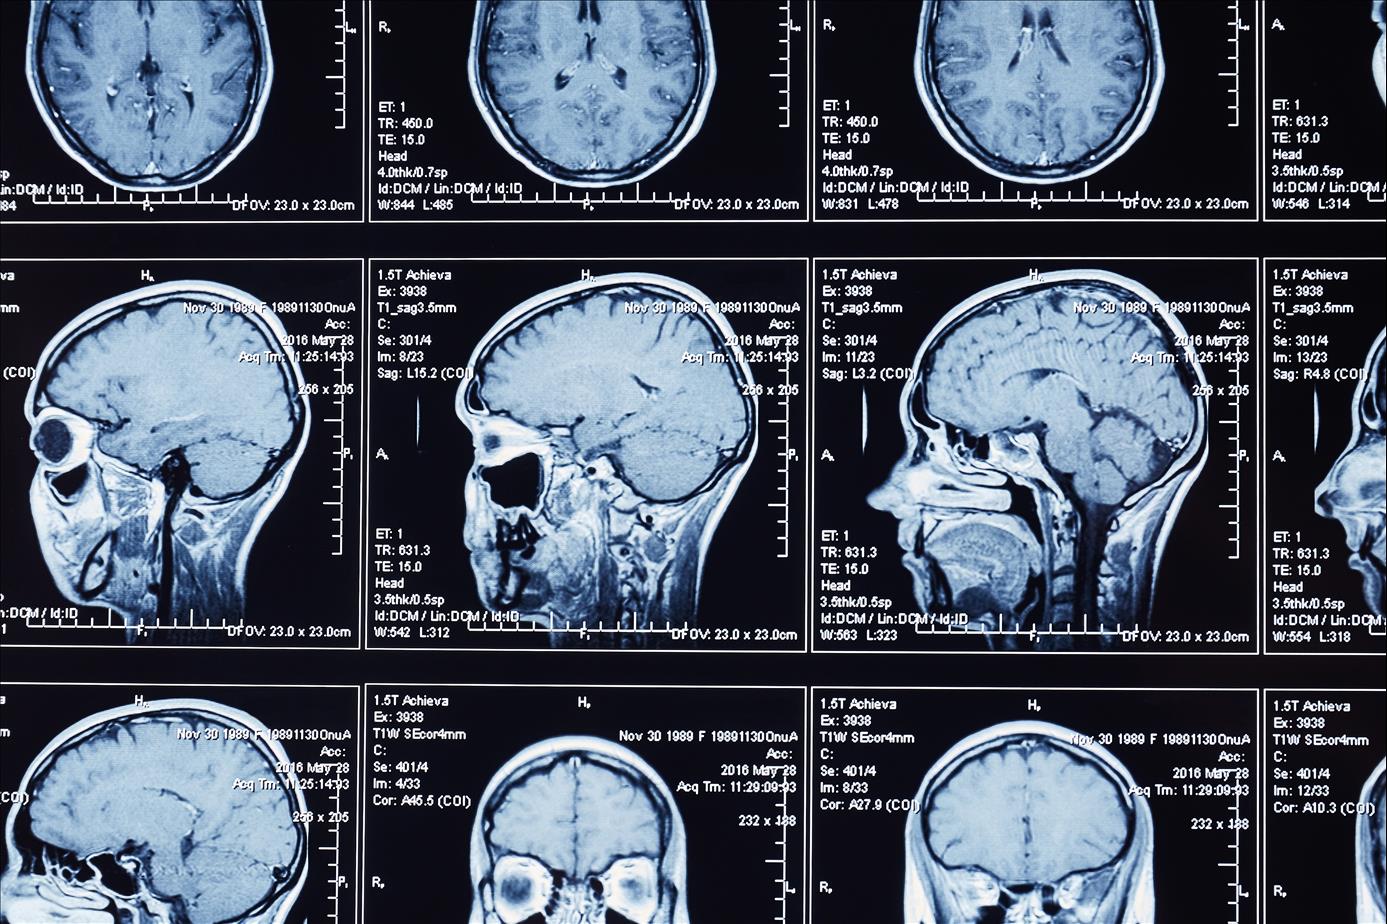

Covid -19 can cause the brain to shrink, reduce grey matter in the regions that control emotion and memory, and damage areas that control the sense of smell, an Oxford University study has found.

Even in mild cases, participants in the research showed “a worsening of executive function” responsible for focus and organising, and on an average brain sizes shrank between 0.2% and 2%.

The peer-reviewed study, published in the Nature journal, investigated brain changes in 785 participants aged 51–81 whose brains were scanned twice, including 401 people who caught Covid between their two scans. The second scan was done on average 141 days after the first scan.